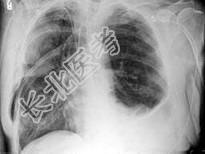

- 单项选择题男,68岁, 胸闷、气短1年余,加重1周, 右胸有手术史,结合CT图像, 最可能的诊断是 ( )

A、右侧气胸并皮下气肿、左侧肺气肿

B、右侧气胸并皮下气肿、左侧肺不张

C、双侧肺气肿

D、右侧气胸并皮下气肿

E、右侧肺间质病变、左侧肺气肿